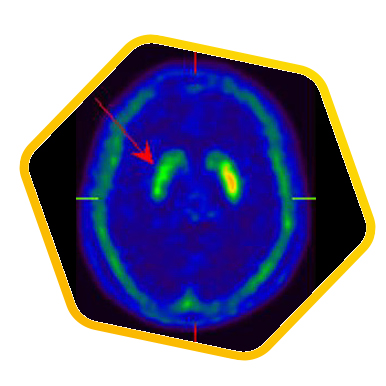

![]() [C-11] Raclopride |

![]() [F-18] DOPA |